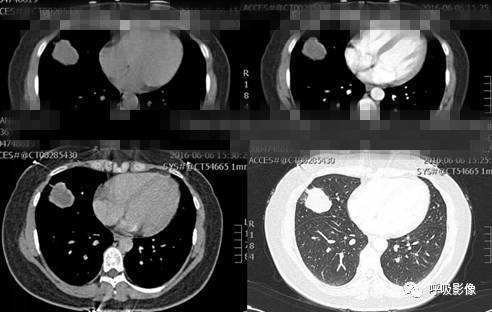

案例三:

简单病史:女,35岁。查体发现肺部占位。胸部CT;右肺中叶外侧段近胸壁处圆形病变,边缘光滑,无毛刺, 增强扫描可见强化。

诊断: 肺良性肿瘤或孤立性转移瘤

诊断依据: 青年女性,右肺中叶结节影,边缘光滑,密度均匀,无明显分叶、毛刺,临近胸膜无受累、肋骨无压迹,不符合肺恶性肿瘤诊断;患者无症状,不符合感染性疾病;病变密度均匀,内无坏死,无卫星灶,不符合结核球诊断。综合考虑肺良性肿瘤或孤立性转移瘤可能性大,病变位于胸膜下,孤立性转移瘤需考虑。病变增强扫描可见血管样强化,提示原发瘤血供丰富,最终病理为绒毛膜癌肺转移。